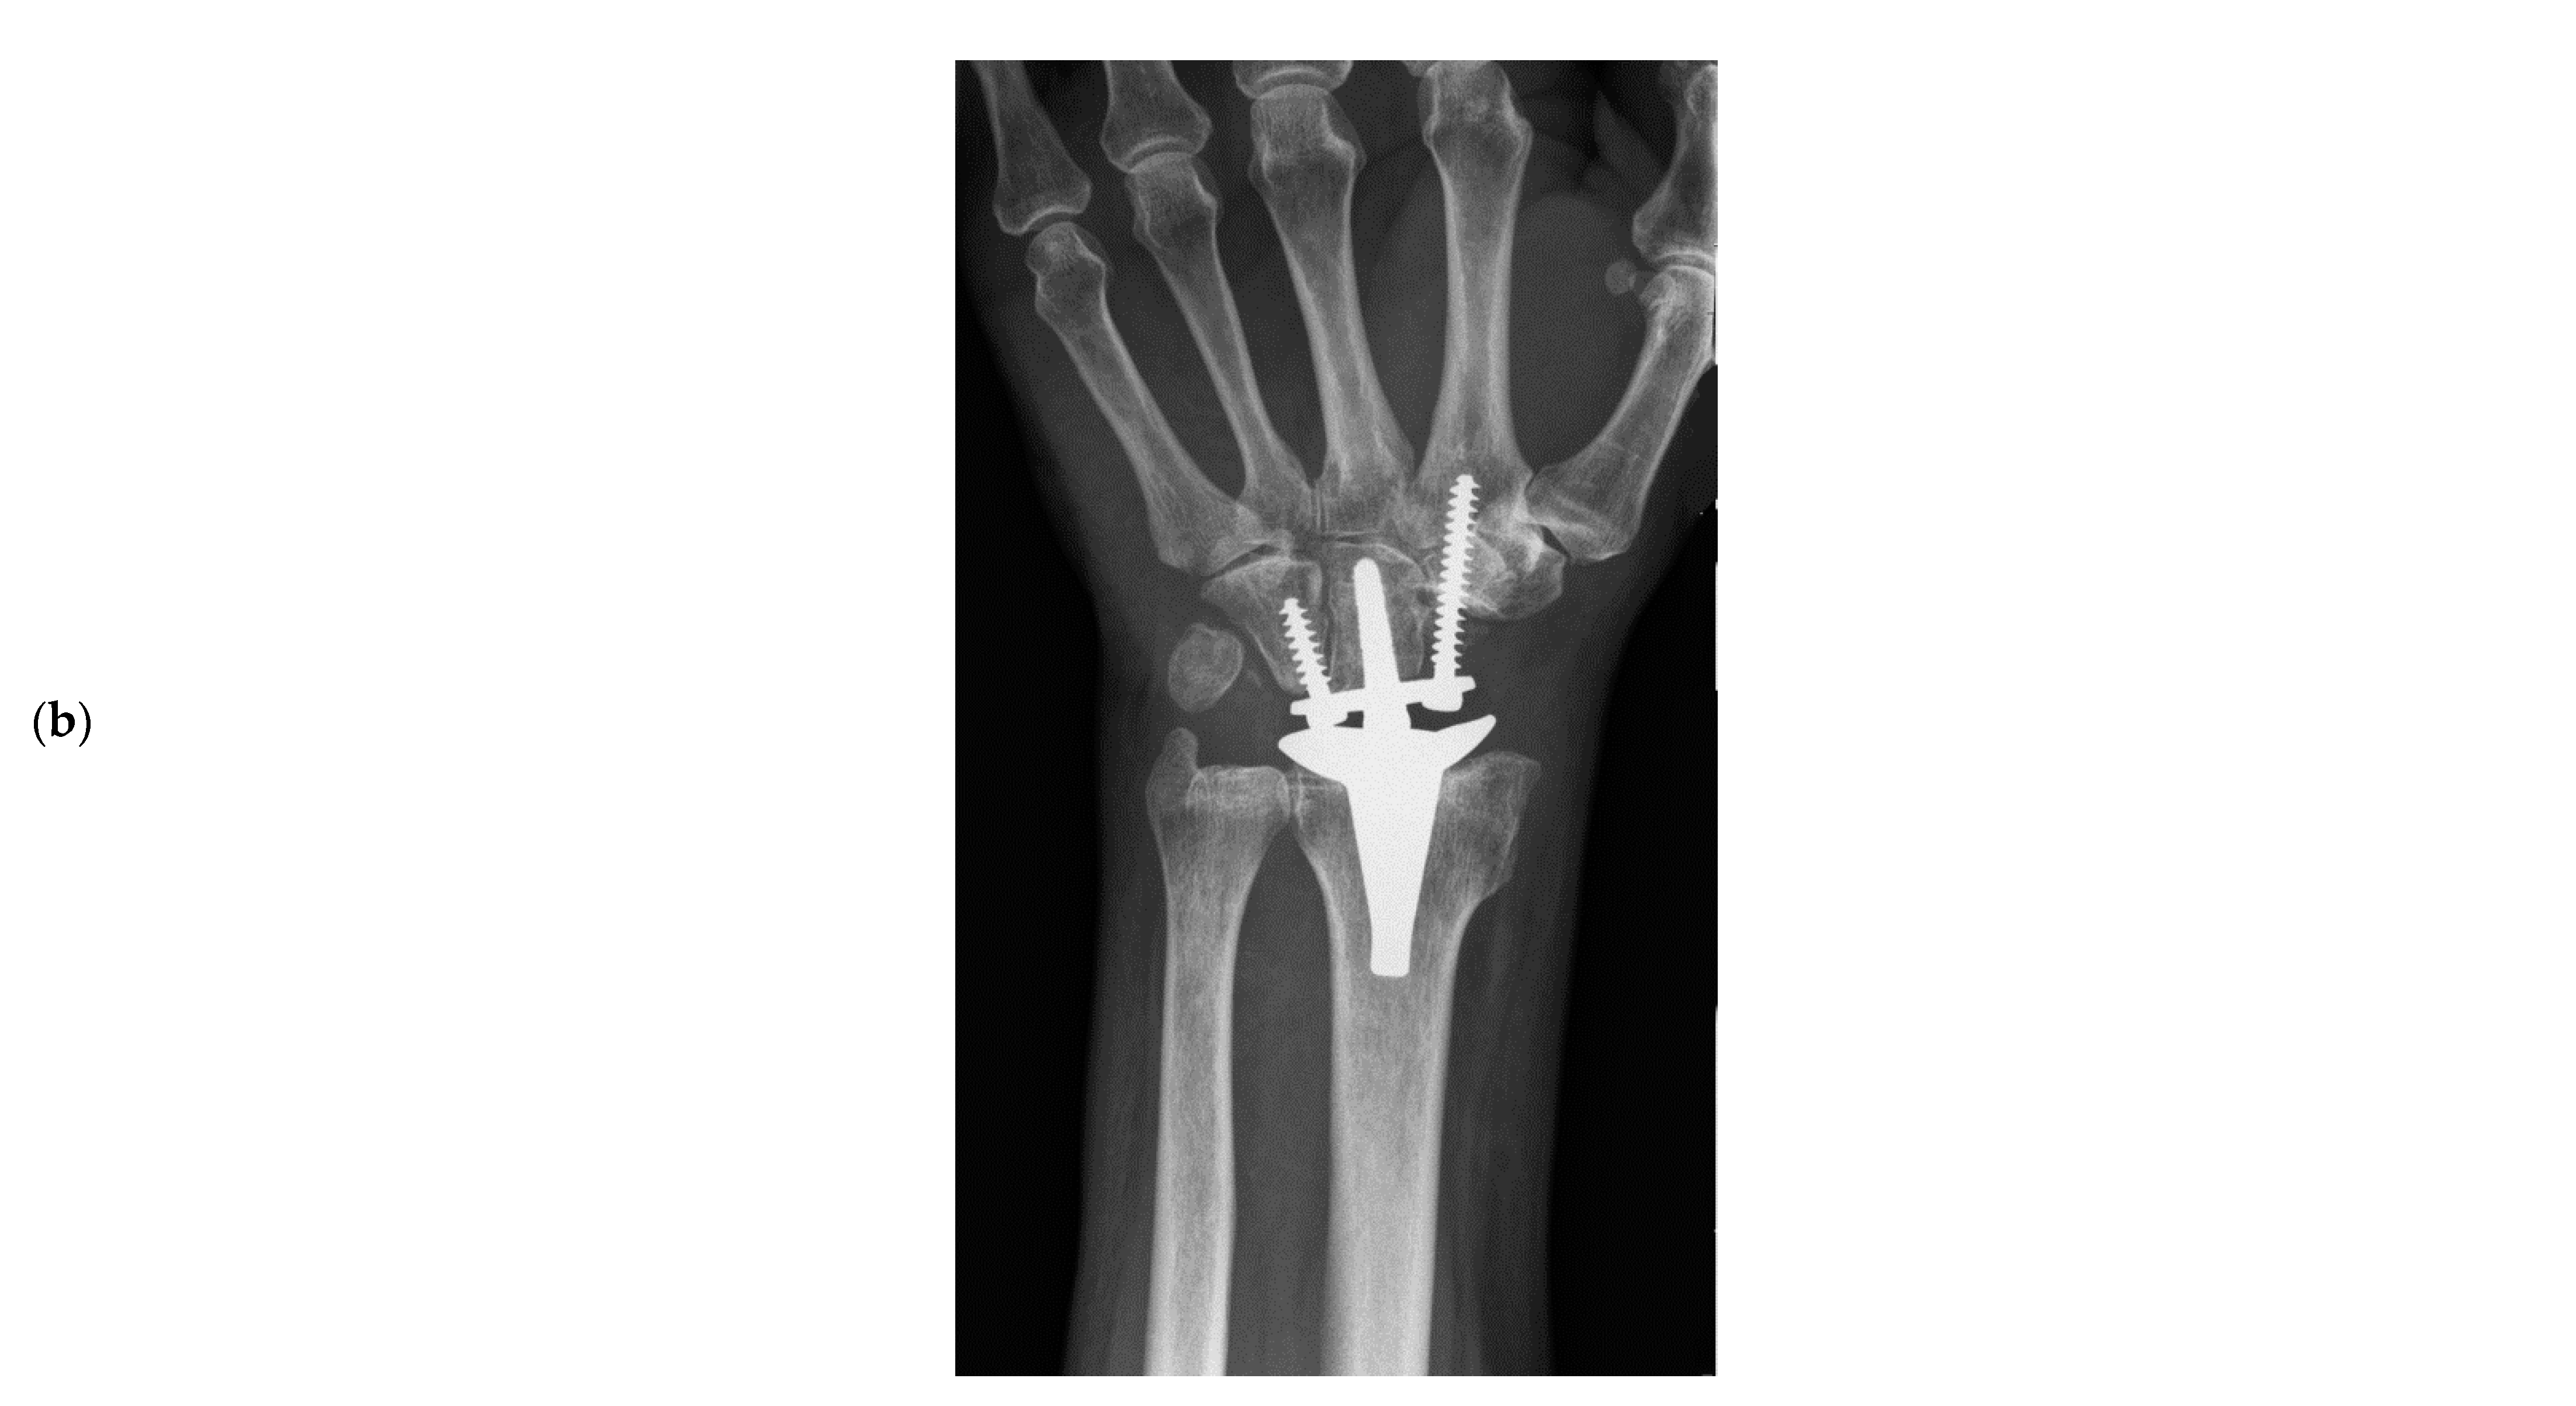

Total Wrist Arthroplasty for Posttraumatic Wrist Osteoarthritis: A Cohort Study Comparing Three Indications

- Froschauer, S.M.; Holzbauer, M.; Hager, D.; Kwasny, O.; Duscher, D. Proximal Row Carpectomy with Total Scapoidectomy vs. Conventional Carpal Resection for ReMotion Total Wrist Arthroplasty. J. Clin. Med. 2021, 10, 1865. [Google Scholar] [CrossRef] [PubMed]